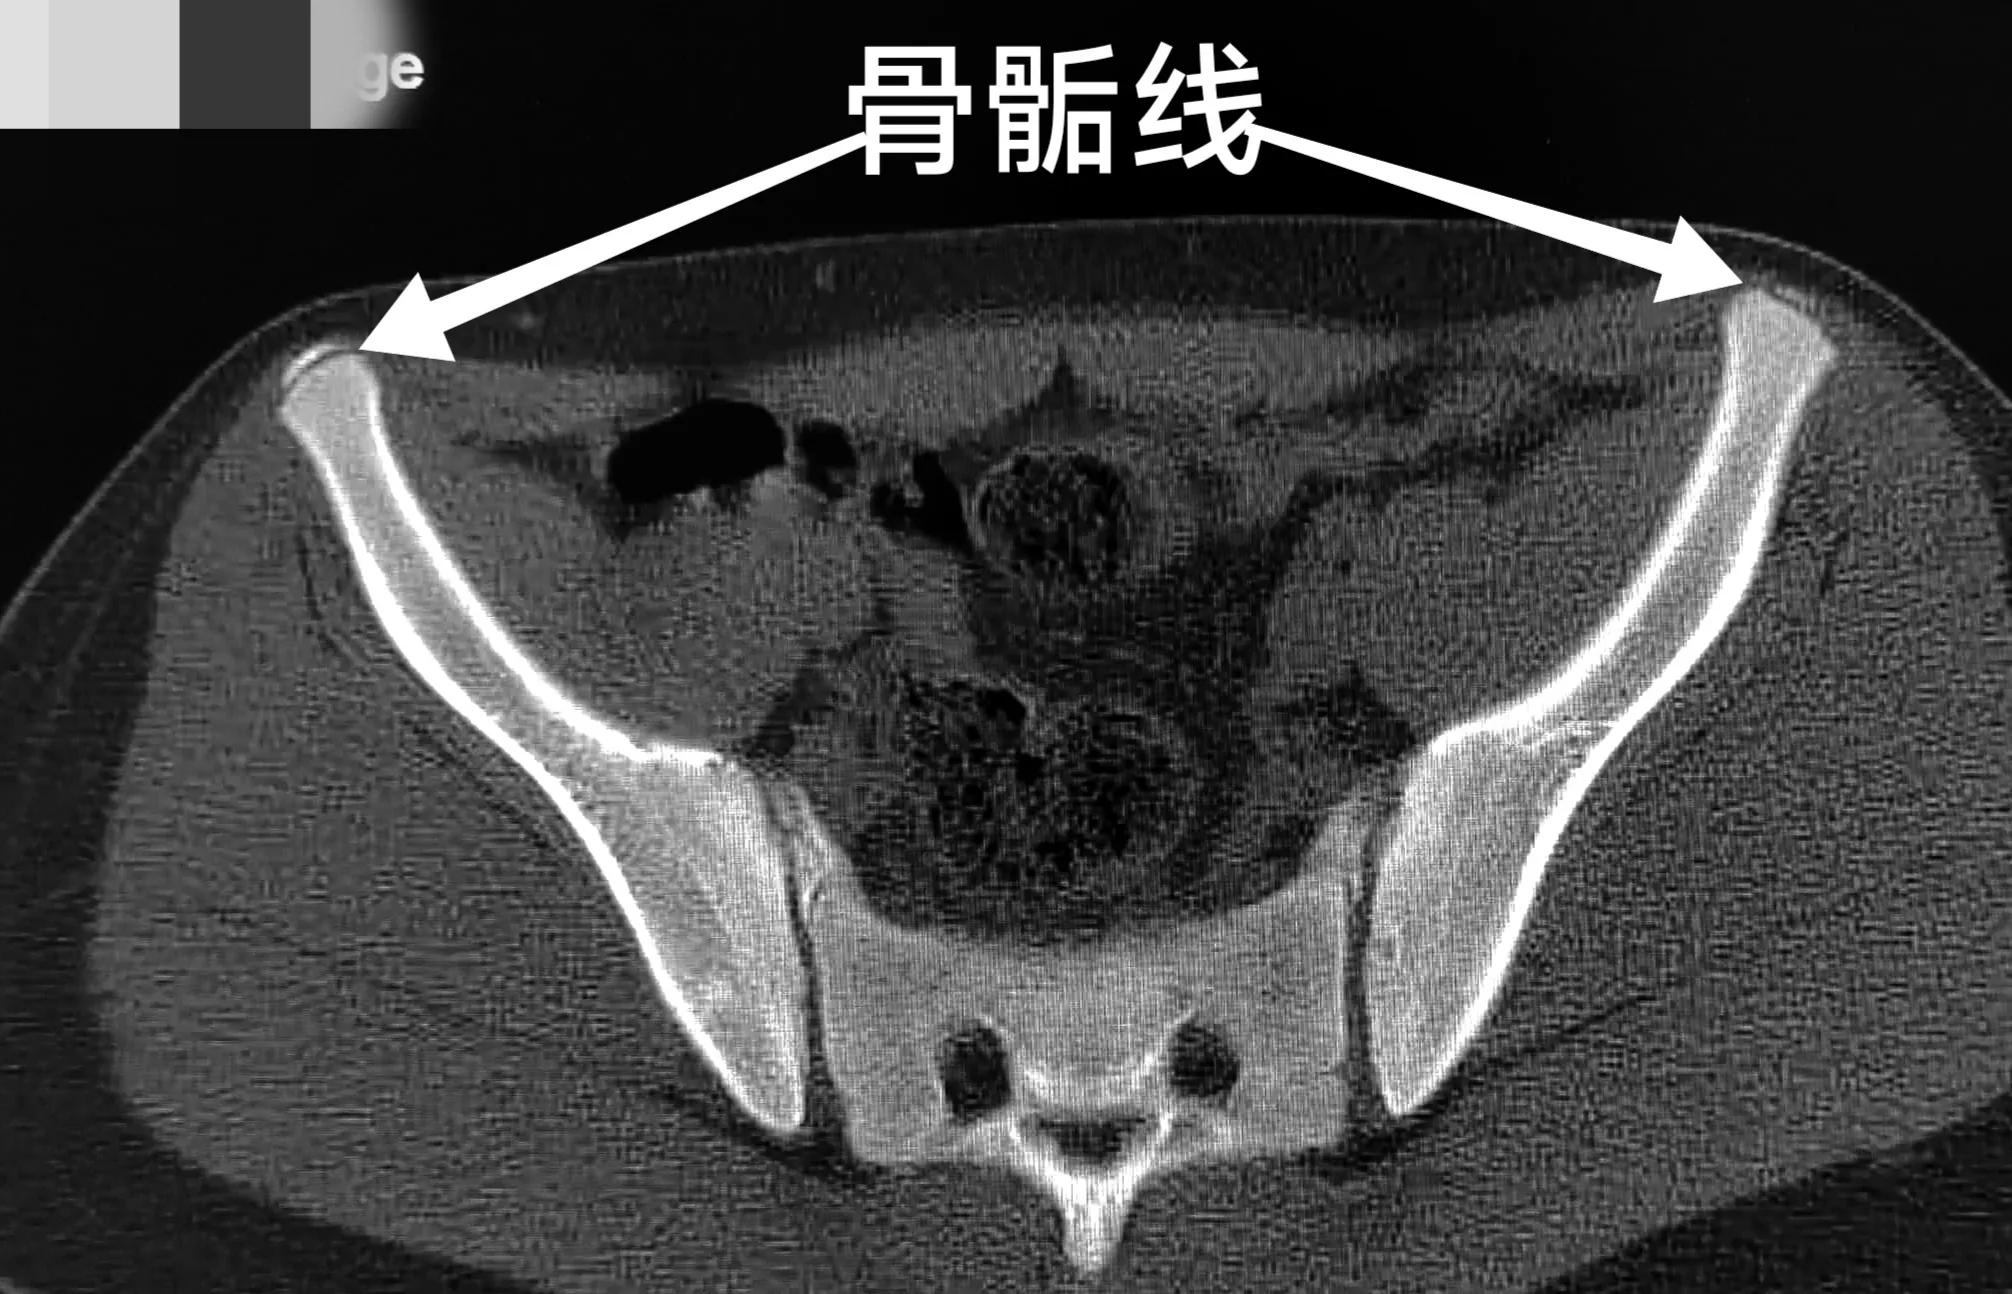

髂前上棘撕脱性骨折多好发于青少年,这个部位有个骨骺线,是生长发育中骨头生长的部位,比较薄弱。